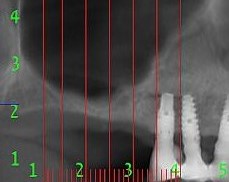

15, 16 Missing, 6 mm subsinus bone height